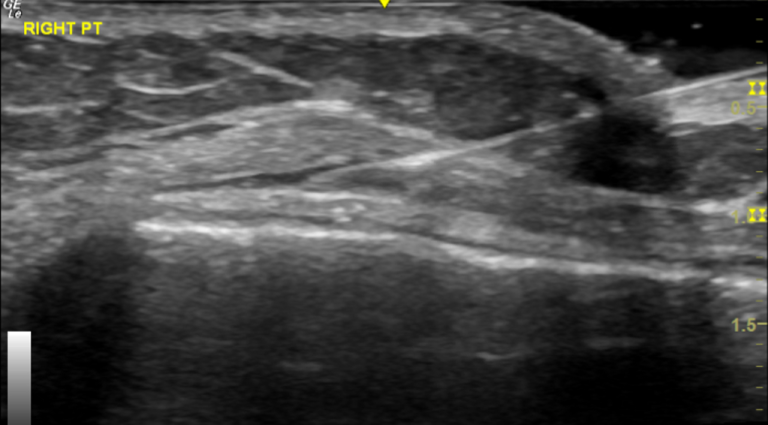

Diagnostic Ultrasound:

Diagnostic ultrasound is very helpful for assessment of iliotibial band friction syndrome. As this is a dynamic modality we we will be able to see the IT band as it moves over the lateral epicondyle of the knee during extension and flexion of the knee. This allows us to evaluate for any thickening of the ITB but also to identify any iliotibial bursitis which is indicated by fluid in the iliotibial bursa.

The ultrasound-guided injection procedure allows very specific targeting of the iliotibial bursa. The bursa is clearly identifiable on ultrasound and for a skilled practitioner the needle is then accurately guided in the ITB bursa which lies superficial of the lateral femoral condyle and underneath the iliotibial band. The accurate administration of steroid also avoids potential weakening of the IT band by inadvertent injection in the body of the IT band which is very realistic possibility if this injection is done unguided.

Diagnostic ultrasound is very helpful in accurately diagnosing the condition and then also allowing accurate injection of a steroid in the inflamed bursa between IT band and lateral femoral condyle